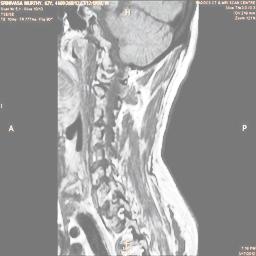

The proposed algorithm uses HSV color space to enhance spinal cord images since this color space offers many advantages such as color separation from intensity, reduced color distortion and efficient enhancement. The algorithm proposed takes advantage of this color space by performing enhancment operation on the intensity or value component and preserving the color information. The first column of Fig. 3 shows the original spinal cord test images followed by the extraction of value component presented in second column. Next, the third column of Fig. 3 shows the value component enhanced using the proposed multirate multiscale retinex algorithm. The modified version of the retinex algorithm presented here is capable of producing high quality reconstructed pictures, far better than the other researchers method.

The developed algorithm presented in the previous section was coded using Matlab Version 8.0. The experiment was conducted by considering poor quality spinal cord images of having various lesions. The first column of Fig. 4 shows the axial view of neck spinal cord images of size pixels, respectively. The second column of Fig. 4 presents the same images enhanced using histogram equalization. As is evident from the results presented, the histogram equalization method performs global image enhancement operation which improves the contrast of an image but at the cost loss in image details. The third column of Fig. 4 shows the MSR based spinal cord image enhancement. It can be seen that from the result presented, MSR scheme improves the details that are not clearly visible in histogram equalization technique. In general, image enhancement achieved by MSR method is better compared to histogram equalization. However, the MSR method voilates gray world assumption. Therefore, the image enhanced by this scheme appears to be grayish. Although, numerous work have been reported for solving the problem due to gray world voilation, no work seems to developed for complete elimination.

The fourth column of Fig. 4 shows the image enhanced using Chao et al. []. It can be seen from the results presented that the reconstructed images of Chao’s method have black spots. The appearance of these dark patches degrades the visual quality of the enhanced image. The image enhanced using proposed multirate multiscale retinex image enhancement method presented in the fifth column of Fig. 4, overcomes the drawback of the Chao’s method. As we can see from the simulation results, image enhancement achieved by the proposed method has improved details with significant contrast enhancement. The enhanced images from the proposed method provides information to physicians, radiologists and researchers for various types of pathology detection.

In order to show the proposed method in more detail, the algorithm is tested with other test images. The first row of Fig. 6 shows the original MRI image of thoracic spine with different views. The second row of Fig. 6 shows the same image enhanced using histogram equalization. Third row of Fig. 6 presents the MSR based enhancement scheme. Fourth row of Fig. 6 indicates Chao’s method of image enhancement. Finally, the reconstructed images using the proposed method is shown in fifth row of Fig. 6. Again, it can be seen from the results presented that the image enhancement using the proposed method is superior compared to other methods. This is evident from the image quality assessment presented in Table 1 using AWE and DWE.